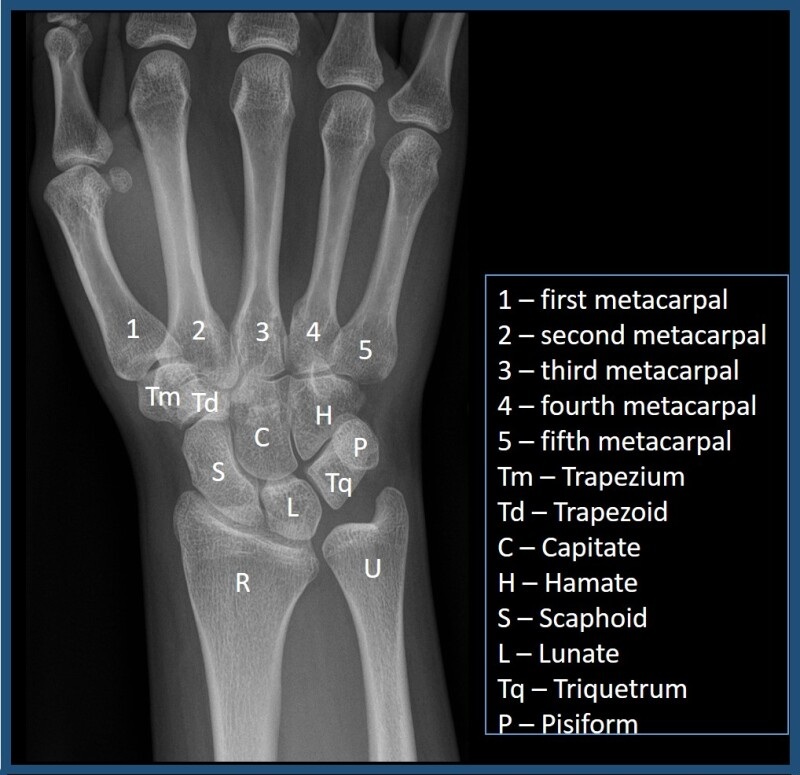

Expand your clinical knowledge with WikiSM.org —a comprehensive resource for sports medicine, MSK exams, and rehabilitation—and MedEdCases.com for real-world, case-based emergency medicine learning